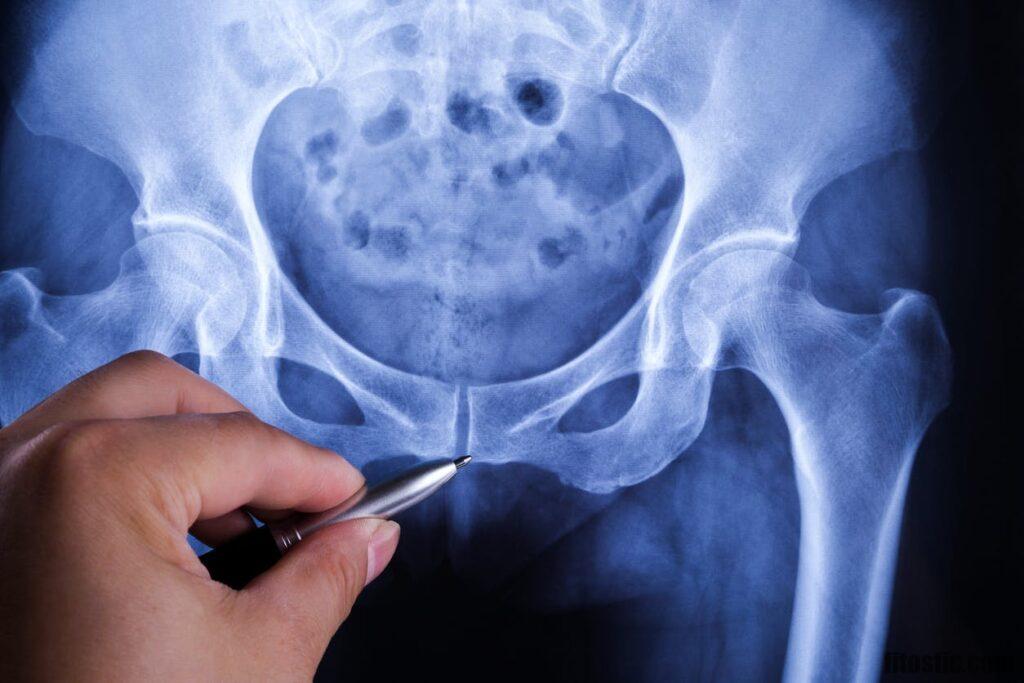

Douleur au coccyx La soulager avec exercices d'ostéopathe. Les symptômes peuvent être variés, mais la douleur au coccyx est généralement le principal symptôme rapporté. Le coccyx‚ situé à l'extrémité de la colonne vertébrale‚ est particulièrement vulnérable aux blessures lors de l'accouchement‚ en particulier en cas d'accouchement difficile ou instrumenté

Estce que c'est grave d'avoir mal au coccyx. La coccygodynie correspond à une douleur du coccyx (du grec odunê [-odynie], douleur) sans irradiation particulière Les cas de fractures du coccyx, liées à l' ostéoporose, existent, mais demeurent extrêmement rares